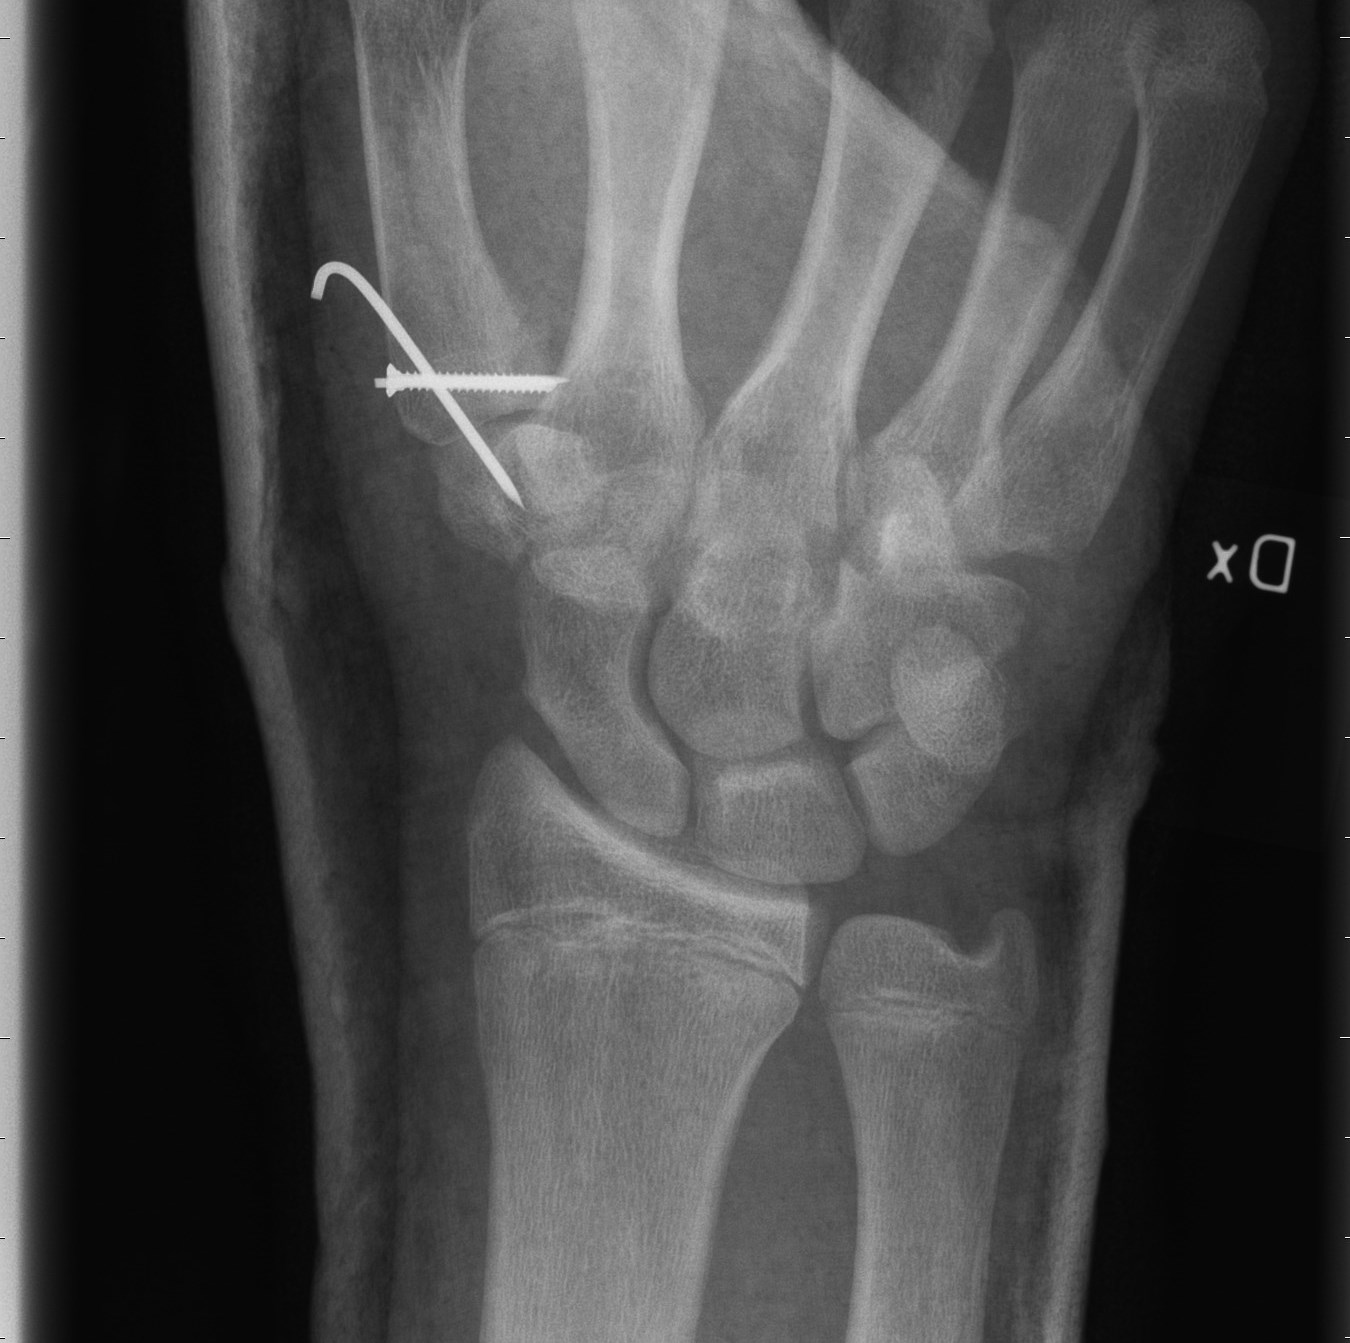

Bennetfraktur

Bennetfraktur är en intraartikulär luxationsfraktur genom basen av metacarpale I. Metacarpalbasen tenderar att luxera genom APL senans dragning i radiell-proxmal riktning. Frakturen behöver därför i princip alltid reponeras och immobiliseras internt med stift. Kan se väldig beskedlig ut på primära bilder men dislocerar succesivt genom senans dragning – klassificeras därför som ”lurig”.

Mekanism vid Bennetfraktur

Bennetfraktur där det ulnara fragmentet i basen på metkarpalen hålls kvar med hjälp av ligament i karpus. På grund av drag i abductor pollicis longus (APL) uppstår nästan alltid en diastas i frakturen. Diastasen i ledytan ger sekundärt artros. Dessa frakturer kräver således exakt fixation – vanligen i form av stift eller skruv.